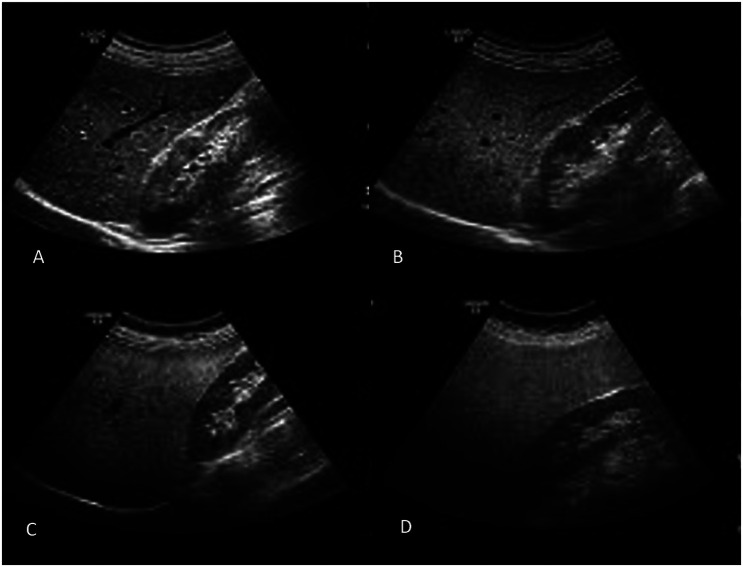

Materials and methods: This cross-sectional study was designed to evaluate the relationship between cholecystectomy and MAFLD. Metabolic dysfunction-associated fatty liver disease was defined by the presence of hepatic steatosis in combination with any of the following conditions: diabetes mellitus (fasting plasma glucose ≥126 mg/dL), overweight (body mass index (BMI) ≥25 kg/m2), or metabolic dysregulation.

Results: A total of 163 participants with BMI ≥25 kg/m2, including consecutive cholecystectomized (N = 83) and non-cholecystectomized (N = 80) subjects, were included. The prevalence of MAFLD was found in 64 out of 83 (77.1%) cholecystectomized patients and in 30 out of 80 (37.5%) non-cholecystectomized subjects (P < .001). When age, gender, BMI, exercise habits, hypertension, diabetes mellitus, and cholecystectomy status were included in regression analyses, we found that only BMI [odds ratio (OR) = 1.155 (95% CI: 1.040-1.283)] and cholecystectomy [OR = 4.540 (95% CI: 2.200-9.370)] were independently associated with MAFLD (both P < .01). ROC analysis identified 10 years as the cut-off, with MAFLD risk being 2.7-7.3 times higher in patients with cholecystectomy for ≤10 and >10 years.